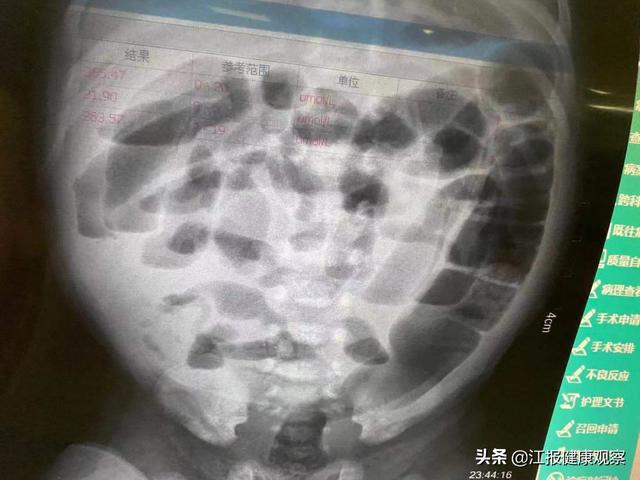

圆圆的到来让新生儿科气氛骤然紧张起来 , 入院时:呕吐较多粪渣及血样物质 , 洗胃后胃肠减压器内仍见较多鲜血样液体 , 解出的大便全是血样便 , 反应差 , 呼吸浅促 , 双肺呼吸音粗糙 , 腹部稍膨隆 , 触诊患儿腹肌紧张 , 呈痛苦状 , 肠鸣音消失 , 肌张力低下……值班一线张妙联医师查看患儿后立即完善急诊腹片检查 , 急诊腹部立卧位片报告肠梗阻!值班二线立即请儿外科钟剑主任急会诊并报告科主任江建华主任医师 , 江主任认为患儿需要立即手术 , 并报告总值班提请新生儿外科郭秋鹏副主任医师进行多学科共同救治 。

腹片显示为肠梗阻